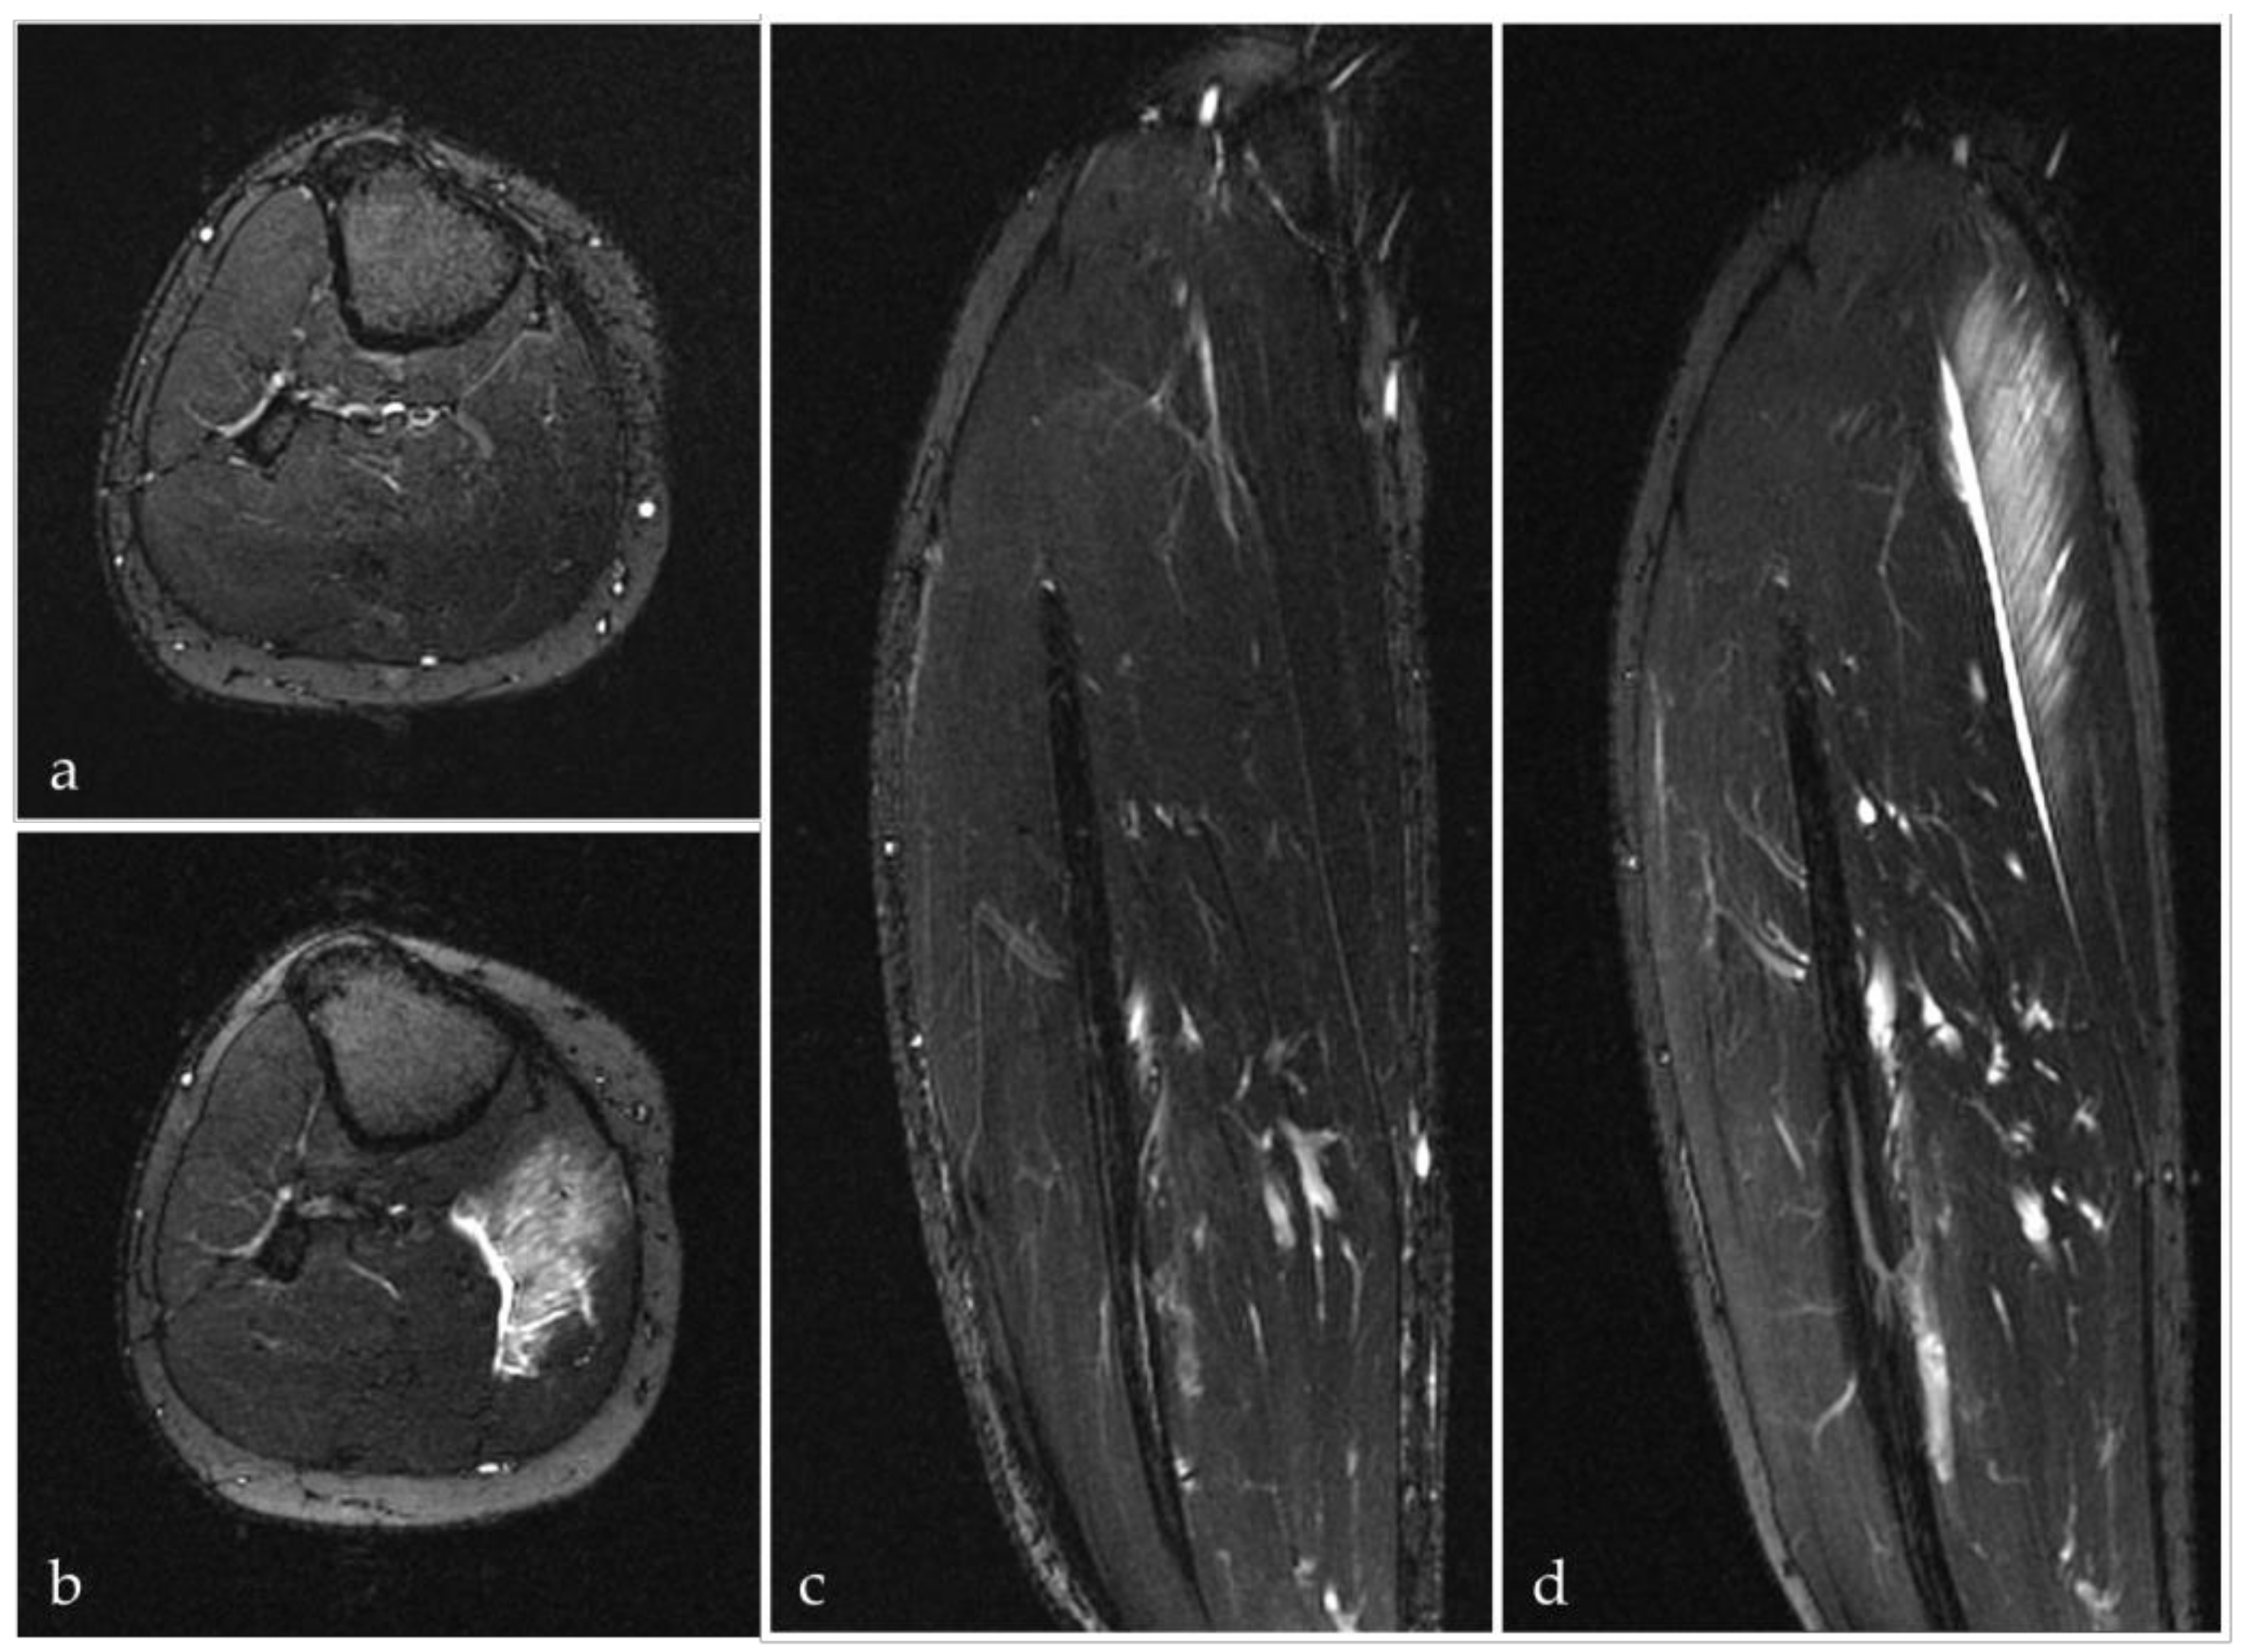

- Hotfiel, T.; Kellermann, M.; Swoboda, B.; Wildner, D.; Golditz, T.; Grim, C.; Raithel, M.; Uder, M.; Heiss, R. Application of Acoustic Radiation Force Impulse (ARFI) Elastography in Imaging of Delayed Onset Muscle Soreness (DOMS): A Comparative Analysis With 3T MRI. J. Sport Rehabil. 2017, 1–29. [Google Scholar] [CrossRef]

- Heiss, R.; Kellermann, M.; Swoboda, B.; Grim, C.; Lutter, C.; May, M.S.; Wuest, W.; Uder, M.; Nagel, A.M.; Hotfiel, T. Effect of Compression Garments on the Development of Delayed-Onset Muscle Soreness: A Multimodal Approach Using Contrast-Enhanced Ultrasound and Acoustic Radiation Force Impulse Elastography. J. Orthop. Sports Phys. Ther. 2018, 48, 887–894. [Google Scholar] [CrossRef] [PubMed]

- Yu, J.Y.; Jeong, J.G.; Lee, B.H. Evaluation of muscle damage using ultrasound imaging. J. Phys. Ther. Sci. 2015, 27, 531–534. [Google Scholar] [CrossRef] [PubMed]

- Kellermann, M.H.M.; Swoboda, B.; Gelse, K.; Freiwald, J.; Grim, C.; Nagel, A.; Uder, M.; Wildner, D.; Hotfiel, T. Intramuscular perfusion response in delayed onset muscle soreness (DOMS): A quantitative analysis with contrast-enhanced ultrasound (CEUS). Int. J. Sports Med. 2017, 38, 833–841. [Google Scholar] [CrossRef] [PubMed]